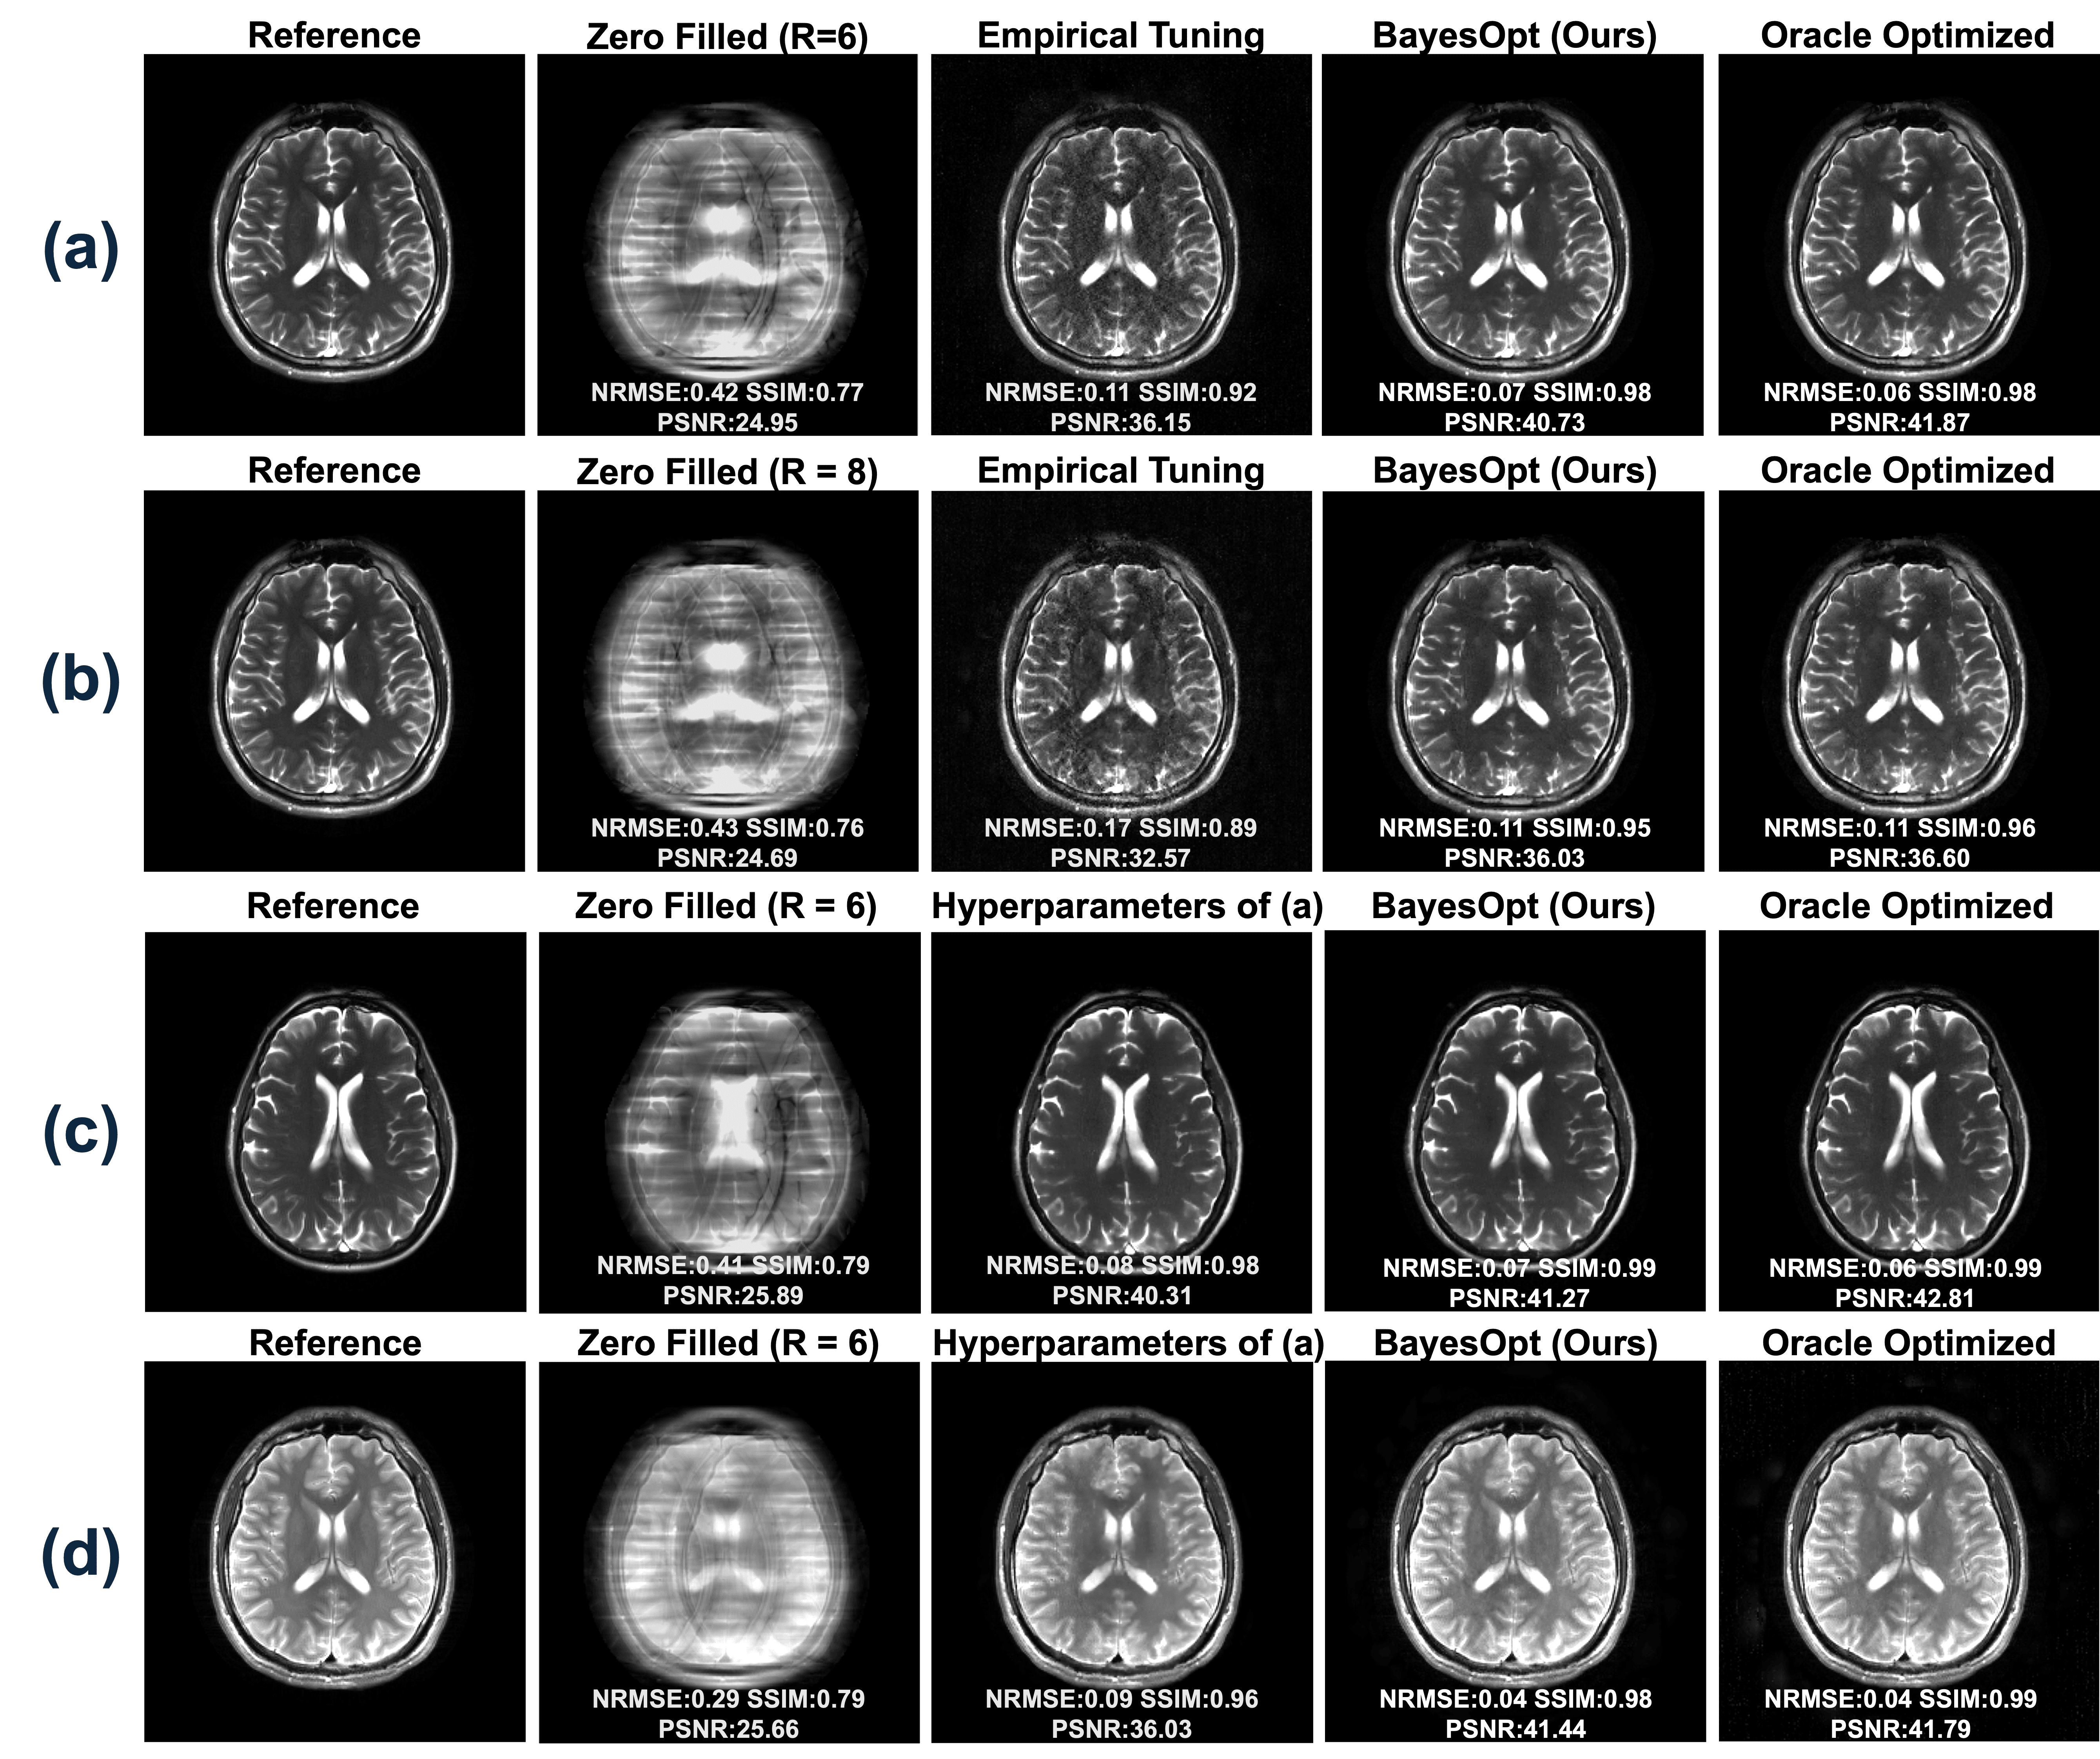

Refer to caption

Figure 3: Method comparisons. (a) Brain volunteer at 3T using bSSFP of 1×1mm21\times 1\ \textrm{mm}^{2} resolution. (b) Brain volunteer at 3T using T2w TSE of 1×1mm21\times 1\ \textrm{mm}^{2} (c) Cardiac volunteer at 0.55T using T2w bSSFP of 1.4×1.4mm21.4\times 1.4\ \textrm{mm}^{2} resolution. (d) Prostate volunteer at 3T using T2w TSE of 1×1mm21\times 1\ \textrm{mm}^{2} resolution. Detailed acquisition protocols are shown in Table 1.

Fig. 3 compares our proposed approach with other model-based iterative and self-supervised deep-learning methods.

For 8×8\times Cartesian undersampled bSSFP brain experiments (Fig. 3(a)), CG-SENSE introduces notable noise across the brain, and 1\ell_{1}-Wavelet, P-LORAKS, and IMJENSE exhibit residual artifacts from the sampling pattern. In contrast, the proposed method shows only minor residual artifacts and achieves a PSNR more than 5 dB higher than the other approaches.

Fig. 3(b) presents results from 20×20\times Poisson undersampled experiments with a central 10×1010\times 10 pixel auto-calibration region. Both CG-SENSE and P-LORAKS show visible non-structured noise in the whole brain. In contrast, 1\ell_{1}-wavelet, IMJENSE, and the proposed bilevel INR display visually artifact-free reconstructions, with our method outperforming others supported by all metrics. INR-based methods (i.e., IMJENSE and ours) benefit from the relatively uniform sampling pattern, which results in non-structural artifacts. These artifacts are easier to remove by INR, because of its strength in learning continuous and smooth function manifolds.

Fig. 3(c) compares methods on a non-gated cardiac dataset at 0.55T, acquired via a T2-weighted bSSFP sequence. The proposed bilevel INR reduces noise and suppresses most motion artifacts by its implicit regularization on continuity. Other methods either fail to remove noise (CG-SENSE, IMJENSE) or retain motion artifacts (P-LORAKS, IMJENSE). The 1\ell_{1}-Wavelet result appears overly smooth.

Finally, for simulated 8×8\times spiral undersampling (Fig. 3(d)), all model-based methods show spiral undersampling artifacts. Our method achieves better metrics and yields nearly artifact-free reconstructions. IMJENSE is omitted here because it only supports Cartesian sampling patterns.